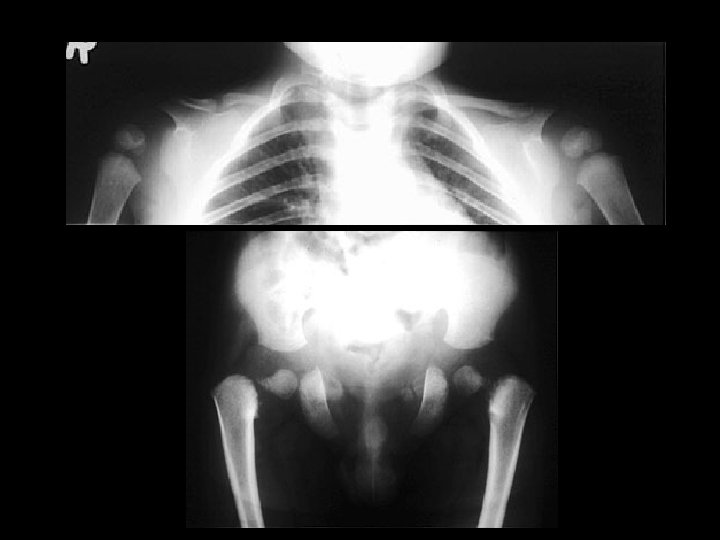

Congenital Reubella w/patent ductus arteriosis • • • Findings: – cardiomegaly, enlarged pulm arteries – longitudinal striations of sclerotic and radiolucent areas at the metaphyses (“celery stalk” appearance) – epiphyseal center not seen – dense, irregular metaphyseal bands most common viral infxn w/bone changes (also CMV) IUGR, TTP, cataracts, sensorineural hearing loss, PDA, pulm art and Ao stenoses

Osteogenesis Imperfecta Type II • Findings: – multiple fractures, bowing and short ribbon-like bones • Type II - lethal - “ribbon bones” and fractures too numerous to count • Disturbances in type I collagen – lack of normal collagen – osteoperosis – fractures – blue sclera • ddx: – NONE! – This is an Aunt Minnie!